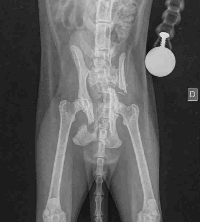

Olá, esse é o Ônix, meu gatinho. Há algumas semanas atrás ele sofreu um atropelamento, desde então a vida dele mudou! Ele tem passado por dores fortes constantes, precisou tomar várias medicações. A princípio não sabíamos exatamente o que tinha ocorrido, mas ele tinhas várias escoriações pelo seu corpinho, um ferimentos na boca que ocasionou a quebra de seu dentinho. Além das dores ele tbm não estava comendo direito, foram vários dias cuidando dele com muito carinho, a veterinária veio examinar ele, e constatou o atropelamento. Por morarmos no interior temos algumas dificuldade de locomoção! E infelizmente naquele momento eu tbm não dispunha de muito recurso. Fizemos o possível, tratando dele da melhor forma possível, aos poucos foi apresentado melhoras, mas estava nítido que algo ainda não estava certo, ele começou a apresentar dificuldade em andar, e de fazer cocô. Foi preciso fazer uma lavagem nele, para tirar cocô que ficou durinho, durante esse processo a veterinária já consegui detectar uma fratura, que estava obstruindo a passagem das fezes. Agora ele está na base de laxante para não ter que fazer um novo procedimento, fui atrás do raio x, e eis que a notícia não foi das melhores, ele tem duas grandes fraturas e ambas impedem a passagem das fezes, E estamos agora atrás de uma cirurgia para lhe dar melhor qualidade de vida, e que seu quadro não piore. Essa cirurgia custa R$ 3.150,00. E eventuais gastos, com consulta veterinária, exames e medicamentos e transporte. Peço a quem puder, ajude com qualquer quantia, Aos poucos espero vencer mais esse obstáculo com esse menino! Gratidão a todos que puderam ajudar. E que não puder financeiramente, ajude compartilhando pfv!